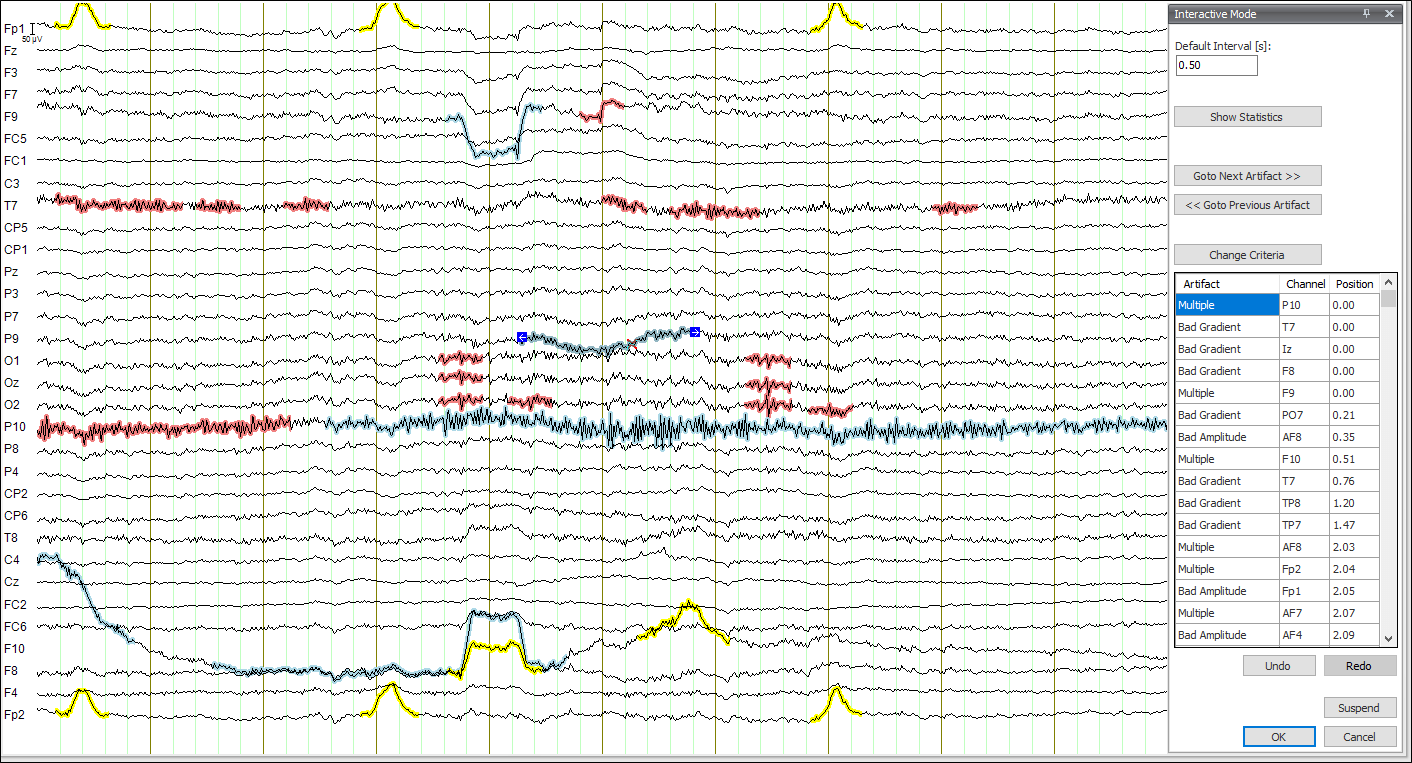

生物医学工程 EEG分析 预处理 Aursus

BME EEG Analysis Preprocessing Aursus Electrode Pop Eeg Electrode “pop” artifact at f3. On eeg pop is marked by a single electrode showing a very. However, the electrochemical instabilities produced by the loose contact can lead to sudden conductance changes which. Scalp electroencephalogram (eeg) records electrical activity generated in the brain. Note that the artifact is not seen in the e1. A common such finding is electrode pop,. Electrode Pop Eeg.

From aursus.github.io